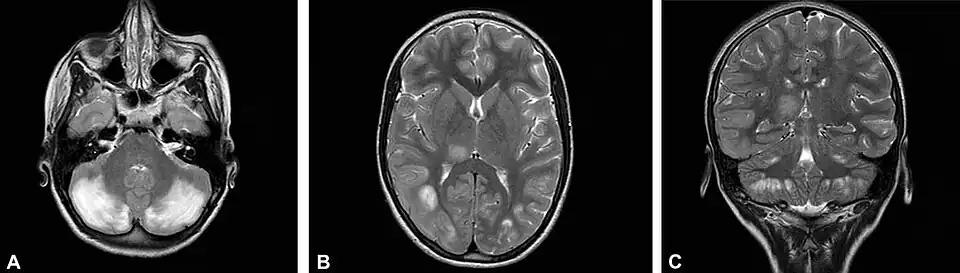

До и после возобновления терапии лейковорином при недостаточности ДГПР

- 1 2 Pappalardo MG, Di Nora A, Giugno A, Meli C, Sapuppo A, Pavone P, Fiumara A (September 2022). Dihydropyridine Reductase Deficiency: Acute Encephalopathy Related to Folinic Acid Treatment Interruption in a Girl. Global Medical Genetics. 9 (3): 247–251. doi:10.1055/s-0042-1756661. PMC 9484871. PMID 36132999.